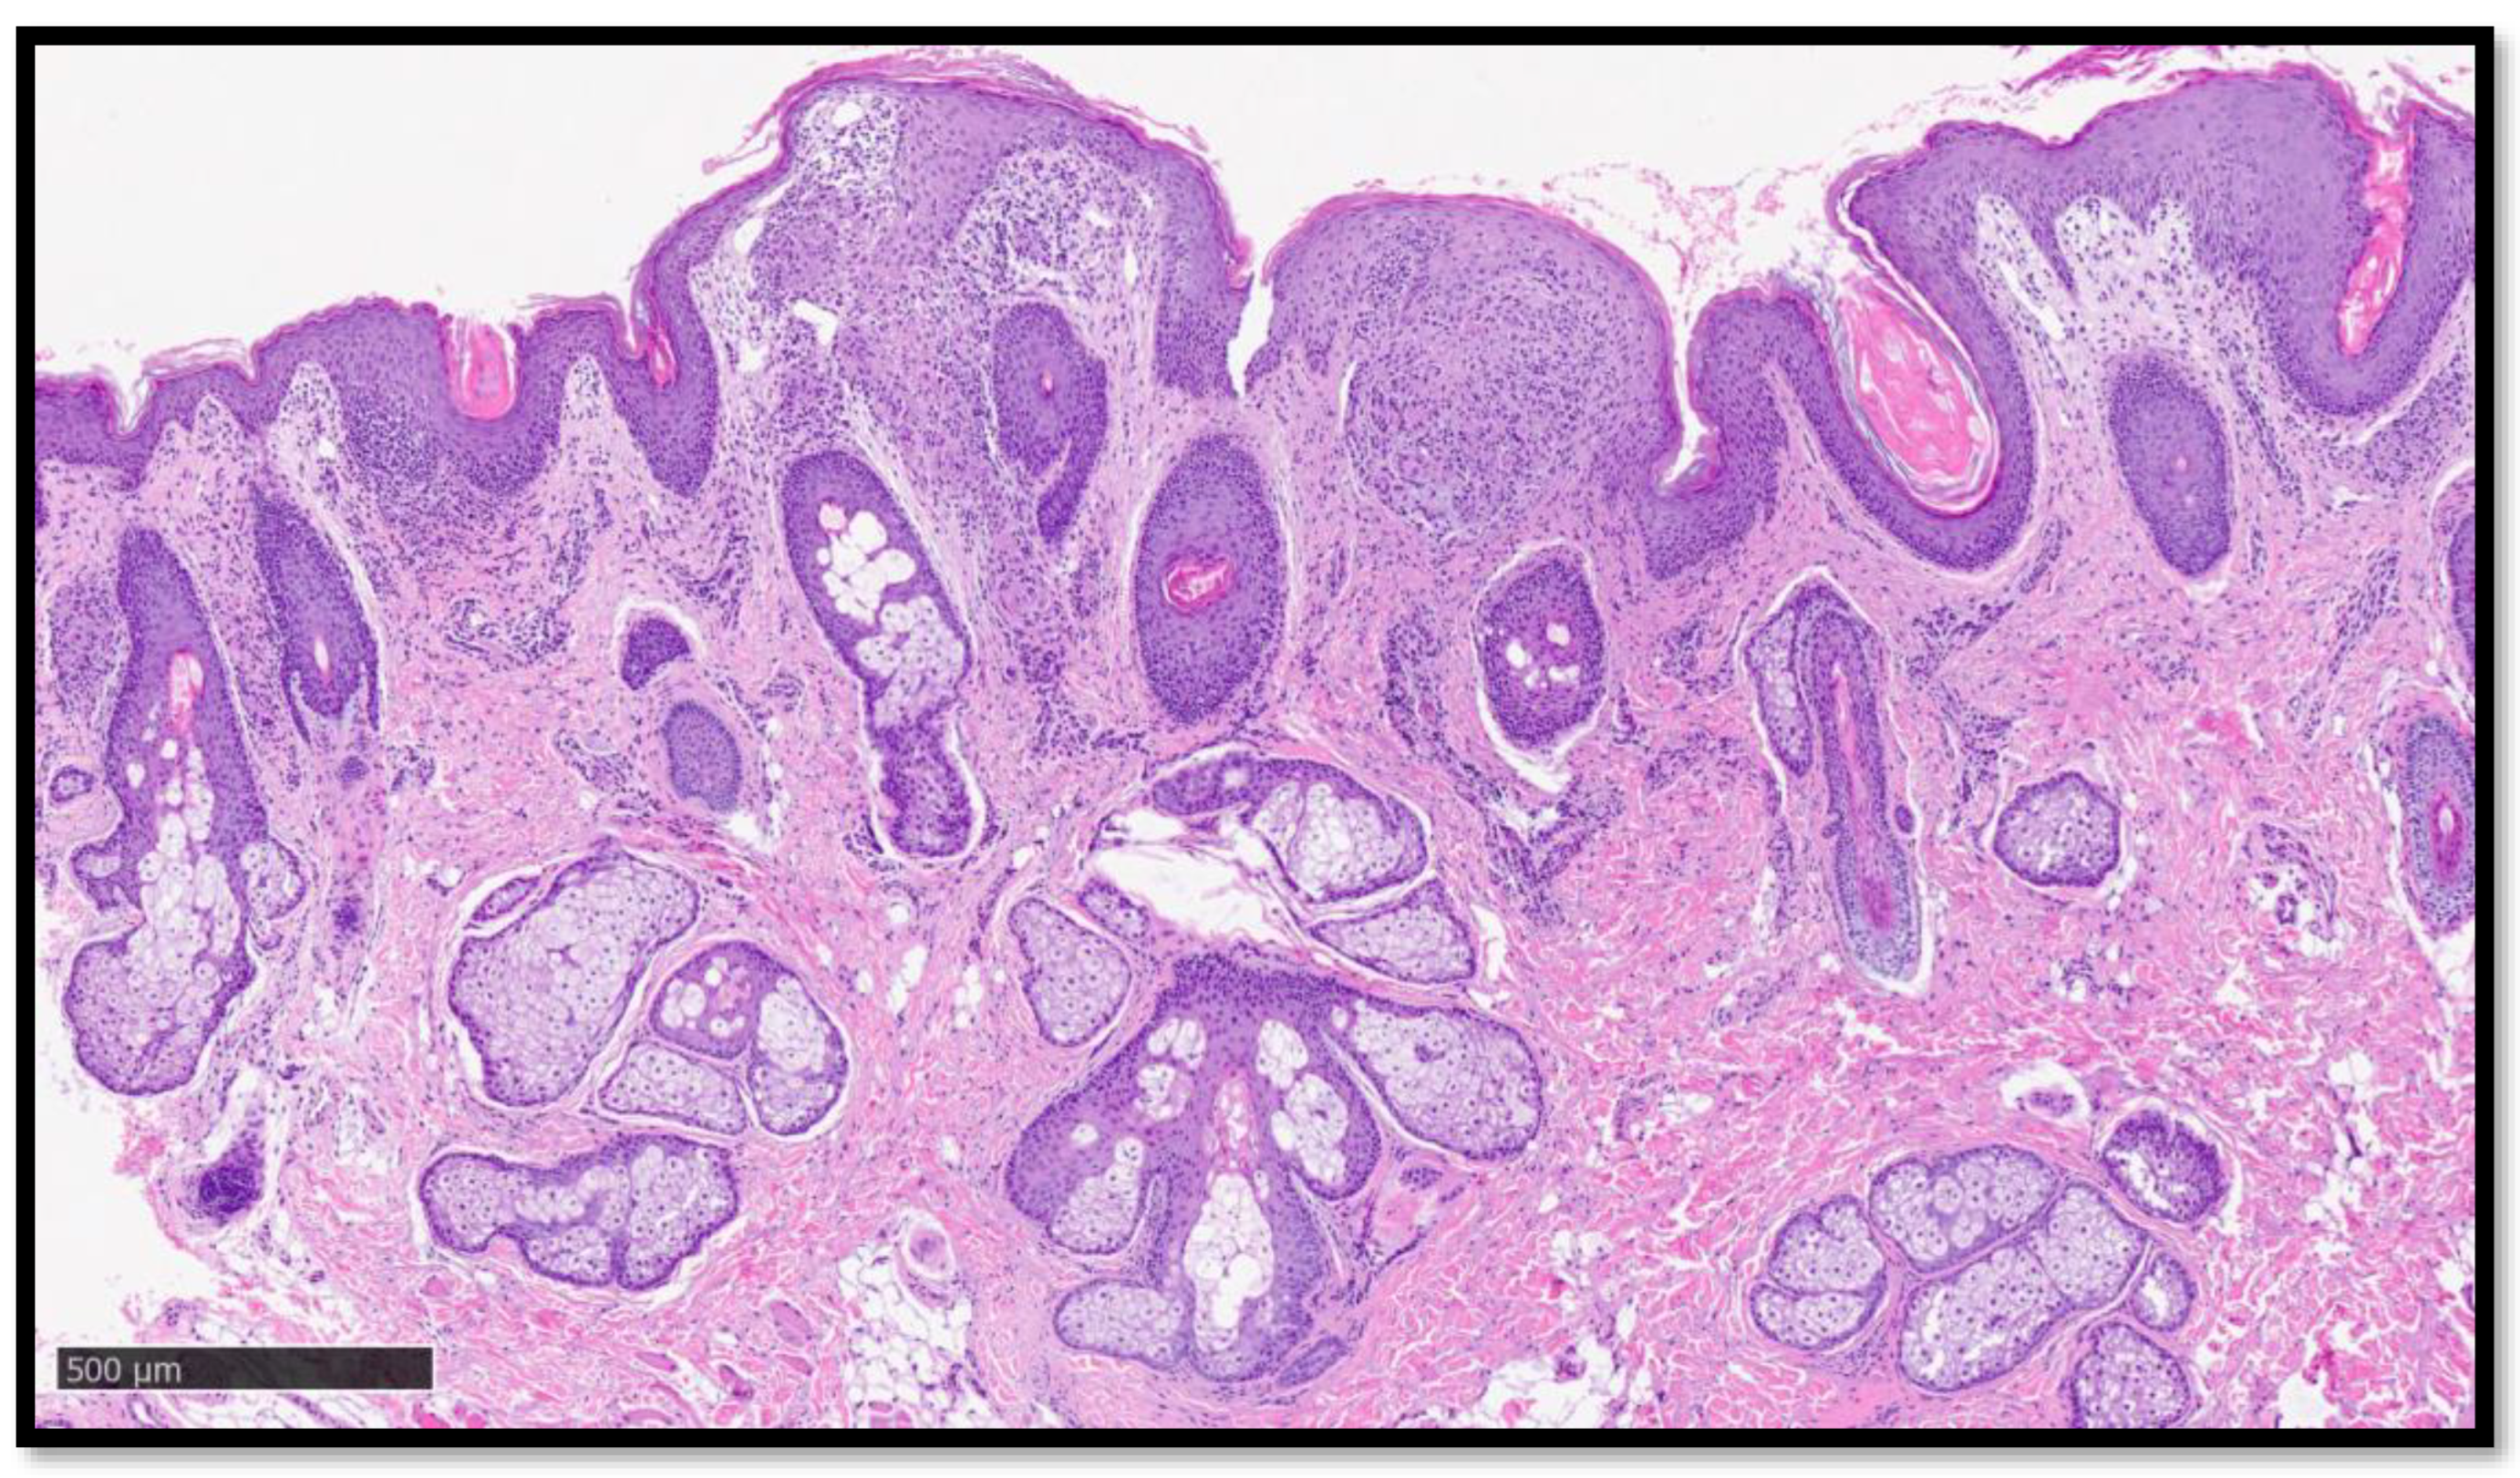

Cazzato, G.; Ambrogio, F.; Foti, C.; Capuzzolo, M.; Trilli, I.; Casatta, N.; Lupo, C.; Carrieri, M.; Daini, D.; Colagrande, A.; et al. Cutaneous Sarcoidosis-like Eruption Following Second Dose of Moderna mRNA-1273 Vaccine: Case or Relationship? Diagnostics 2023, 13, 1286. https://doi.org/10.3390/diagnostics13071286